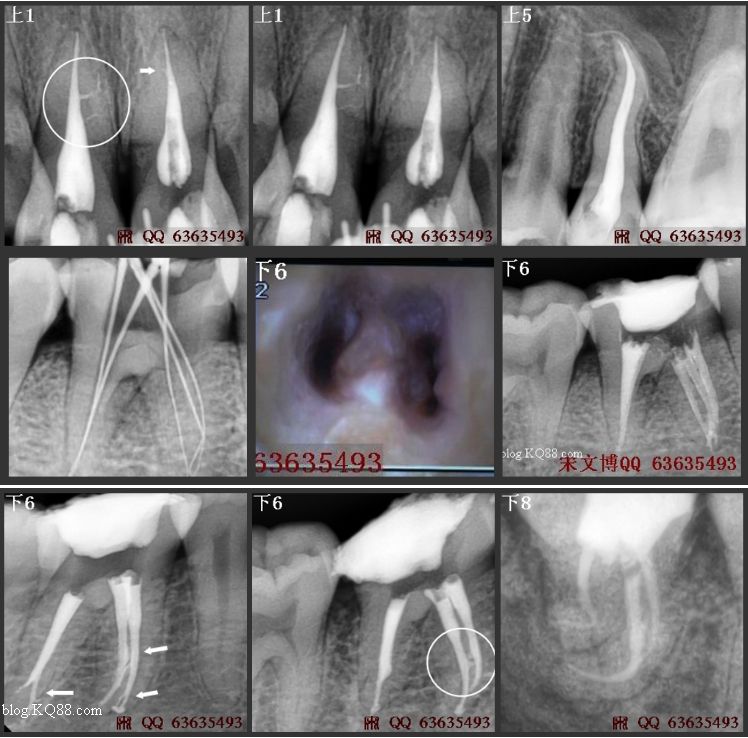

成人恒牙有28~32顆(如圖01),第一磨牙,它是體積較大、牙根和根管解剖最復(fù)雜的;“六齡牙”也是最常需要治療而被了解的又最少的后牙。它的根管治療失敗率較高,但毫無疑問它是最重要的牙齒之一(如圖02/03/34)。

根管口永遠(yuǎn)位于顏色較暗的髓室底和顏色較淺的髓室壁的交界處,且通常處在暗色底線角的頂點(diǎn)上(如圖09/16)。直到暗色髓室底和淺色髓室壁的交界清晰可見,通路預(yù)備才算充分。如果看不清楚這一交界,說明髓室頂還沒有被全部磨除。

根充操作是除了嚴(yán)密充填之外還需要注意兩點(diǎn):①髓腔內(nèi)不可殘留糊劑,②牙膠齊平根管口或根管口下約2mm。整個(gè)RCT操作過程應(yīng)該緊張有序、干凈利落?。。。ㄈ鐖D17/32)………………

老版的教科書記載上頜磨牙通常為3個(gè)牙根和3個(gè)根管,近來很多資料表明上頜第一磨牙存在4個(gè)根管的比例大于70%,用放大鏡或手術(shù)顯微鏡放大以尋找額外根管,MB2發(fā)現(xiàn)率為90%以上(如圖27/29/33/34)。作為施術(shù)者心中不了解牙齒,根管治療中遺漏根管,就根本談不上根管治療的成功。(詳見本文開頭部分)

牙醫(yī)師應(yīng)該始終考慮在近中頰根中有兩個(gè)根管,直到證明只有一個(gè)根管為止。